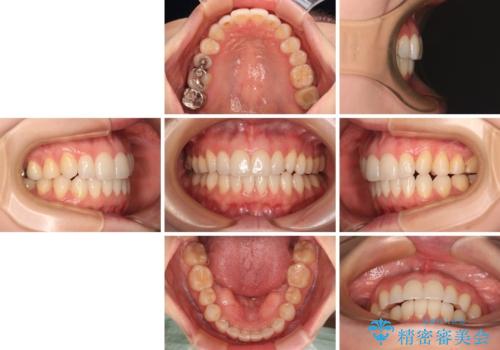

- 前歯のデコボコや八重歯の様になっていることを気にして来院された患者様です。

犬歯捻れて前方に飛び出しており、下顎前歯もそれに沿うようにデコボコとなっていました。

IPR(歯と歯の間を削る処置)によりスペースを獲得して上下顎前歯のデコボコを改善し、前歯が前方に突出しないように設定した上で、インビザラインにて矯正治療を行うこととしました。